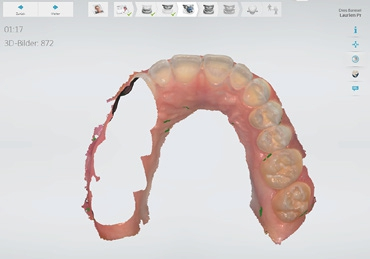

Umfassendere Restaurationen bis hin zu mehrgliedrigen Brückenkonstruktionen, Ganzkieferabformungen, Schienen sowie kieferorthopädische Modelle können im digitalen Workflow kosteneffektiv hergestellt werden. Durch die dreidimensionale Darstellung der Behandlungssituation am Bildschirm mit Abbildung der Zahnstruktur und Gingivatextur kann eine sofortige Qualitätskontrolle vorgenommen werden. Durch den Einsatz neuer plastischer Verdrängungsmaterialien ist auch die bisher problematische Abformung subgingivaler Bereiche gelöst.

Die Implantatprothetik ist einer der Bereiche, in dem die digitale Abformung eine große Erleichterung für den Zahnarzt darstellt. Die Übertragung der Implantatsituation im Mund war bisher für Patienten und Arzt mit konventionellen Methoden unkomfortabel und schwierig. Durch lange Übertragungspfosten war gerade im Molarenbereich das Entfernen der Abformung häufig schwierig. Zudem war die gleichzeitige Abformung von Implantaten und Zähnen durch Materialverziehungen oft nicht in allen Bereichen präzise, sodass Wiederholungen der Abformung nötig wurden. Diese Problematiken liegen bei der digitalen Abformung nicht vor. Je nach System wird zunächst der Restkiefer inklusive der offenen Implantatschraube gescannt, um das Emergenzprofil darzustellen. Die Übermittlung des Emergenzprofils ist eine Information, die zuvor dem Labor nicht zur Verfügung stand und funktionell wie ästhetisch hochwertigere Ergebnisse ermöglicht. Anschließend wird ein zu Implantatsystem und Implantatgröße passender Scanpfosten eingeschraubt, um die Implantatposition zu übertragen. Dieser wird ebenfalls gescannt. Die Software des Scanners rechnet diesen automatisch in den ersten Scan ein. Nach Abformung des Gegenkiefers und der digitalen Bissnahme ist der Vorgang der Abformung beendet und die Daten können ins Labor versandt werden. Sollten weitere präparierte Zähne in dieser Abformung enthalten sein, können diese natürlich einzeln präzise abgeformt und sofort im Monitor überprüft werden. Auf weitere gnathologische Vermessungen gehen wir hier nicht ein, diese sind aber natürlich analog wie digital möglich.